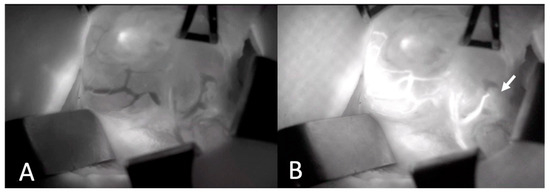

Two experienced board-certified endocrine surgeons performed the operations. For all patients, the conventional subcapsular thyroidectomy approach was used. After a Kocher incision, the subcutaneous tissues and platysma were divided with electrocautery. Subplatysmal flaps were then raised inferiorly extending into the sternal notch and superiorly extending to the thyroid cartilage. The strap muscles were divided and retracted laterally. The right and left thyroid glands were mobilized laterally by blunt dissection and using electrocautery. Retracting the thyroid lobe medially, the middle thyroid vein is identified and ligated. The anterior branches of the superior thyroid artery were dissected and ligated taking care not to harm the external branch of the superior laryngeal nerve. The superior parathyroid gland was then identified by a thorough examination of the superior pole of the thyroid. Then, the inferior parathyroid gland was searched around the inferior pole. Before any dissection, the presumed parathyroid glands were seen with the naked eye. On the opposite side, a similar procedure was used to ensure that as many parathyroid glands as possible could be seen. A solution of ICG (VerdyeTM, Diagnostic Green Ltd., Athlone, Ireland) was created by dissolving 25 mg of powdered ICG in 10 mL of distilled water. For each ICG study, 1 mL of the solution was injected, and the IV line was washed with 10 mL of saline. The vascular supply of the detected parathyroid glands was visualized using SPY-PHI camera (Stryker Corp. Kalamazoo, MI, USA) (Figure 1). All parathyroid glands identified by the SPY-PHI camera were counted and their locations were recorded. The vascular supply of each gland was noted, and dissection was continued accordingly, taking care not to harm any vascular branch supplying parathyroid glands. Thyroidectomy was then completed, and the specimen was removed en-block. An additional 1 mL of ICG was injected and under fluorescence mode, the perfusion of parathyroid glands was visualized (Figure 2). The perfusions of parathyroid glands were compared to the trachea in SPY Fluorescence mode using the fluorescence intensity measurement property. If one gland seemed to be poorly perfused, under direct visualization of the SPY-PHI camera, another 1 mL of dissolved ICG was injected, and the change in fluorescence intensity was inspected in SPY Fluorescence mode. If the gland showed less than 25% increase in fluorescence intensity, the gland was assumed to be nonviable and was excised and autotransplanted. Additionally, the removed thyroidectomy specimen was also imaged using SPY-PHI camera for any parathyroid gland. If found, they were reimplanted.

Figure 1. Intraoperative Images of Thyroid Gland and Parathyroid Gland Vascularization Before (A) and after (B) ICGA. Arrow depicts lower parathyroid gland with intact vascularization (ICGA: Indocyanine green angiography).